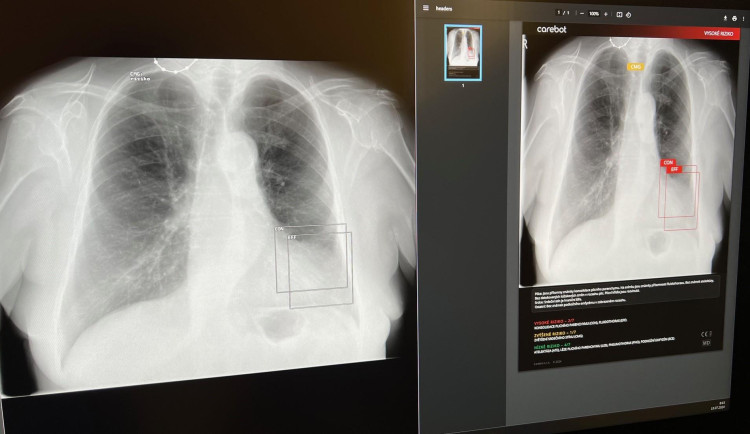

Umělá inteligence mění způsob, jakým se poskytuje zdravotní péče. Jednou z posledních novinek v oblasti medicíny je systém Carebot, který byl nasazen na radiologickém oddělení Nemocnice Tábor.

Systém Carebot využívá pokročilé algoritmy umělé inteligence k rychlejší a přesnější analýze plicních snímků. Tento přístup umožňuje včasné odhalení zdravotních problémů a zahájení odpovídající léčby, což zvyšuje šance pacientů na úspěšnou rekonvalescenci.

„Jsme nesmírně hrdí na zavedení systému Carebot v naší nemocnici. Počet radiologických vyšetření neustále roste, ale počet lékařů zůstává těžko zděditelný. Umělá inteligence je proto žádaným partnerem, díky kterému je lékař schopen zvládnout velký počet vyšetření v požadované kvalitě,“ vysvětluje Tomáš Jindra, primář radiologického oddělení.

První data ukazují, že systém Carebot nejenže urychluje screening plic, ale také zvyšuje jeho úspěšnost. Členové týmu na radiologickém oddělení dosahují vyšší přesnosti v detekci zdravotních potíží ve srovnání s lékaři, kteří systém nevyužívají. Tyto výsledky potvrzují, že moderní technologie mohou hrát klíčovou roli při zlepšování zdravotnické péče.